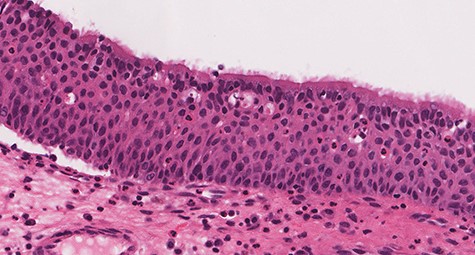

Histologic sections show an endophytic (inverted) pattern that grows downward into the underlying stroma (Fig. 4). The epithelium consists of hyperplastic squamous epithelium (Fig. 5) and ciliated columnar cells admixed with scattered mucocyets (goblet cells) (Fig. 6). The cells have a bland appearance and uniform small nuclei. No cytologic atypia, increased mitotic activity or necrosis seen. Mixed inflammatory cells are dispersed within the epithelium and stroma.

![Section of IP (hematoxylin and eosin [H&E] stain; ×29).](https://oupdevcdn.silverchair-staging.com/oup/backfile/Content_public/Journal/jscr/2020/8/10.1093_jscr_rjaa180/1/m_rjaa180f4.jpeg?Expires=1768215475&Signature=QmVacpIIfI1DV9jAlGaE1Tm9jahPyGfO1Ak4PqzqFm2a72hfuv0vgQ9pinaI8DYl2nWFcBqNe35AWimZPypVp-taU3Z2vcuv6VK64FS4-67clY-oaa0p0BA3yQXAlDlQwBc6maiYx3y0oMbuoPFfX2WhQvgd58Ma~nHTHei5OEJDWJGI5SIe5yU5GwcsQsZ30wfsHXn4kcr2KQmUzWBsXY6yMneptM5Syt3qSk3y0HFQkmAuFRIVFTW2KKYwIP092WxMOuOhrlZ7~hUcTsYxm4baxo2UU89-0bhJCDpNzSTyte4N71f1K2VZx9hCPsiL6tyTJZnAahoXRr9BqubBxQ__&Key-Pair-Id=APKAIYYTVHKX7JZB5EAA)